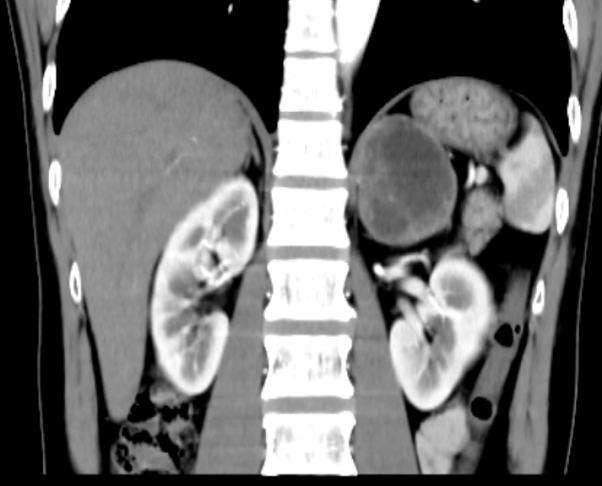

近日,我院接诊一位47岁患者王某,因持续头痛、头晕4天前来就诊。经CT检查发现,左侧肾上腺区存在一类圆形混杂密度肿块,大小约5.2cm×7.8cm×6.1cm,边界清晰,密度不均,增强扫描显示不均匀强化,内部可见片状无强化坏死区,初步诊断为嗜铬细胞瘤。